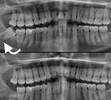

Implant tedavisi